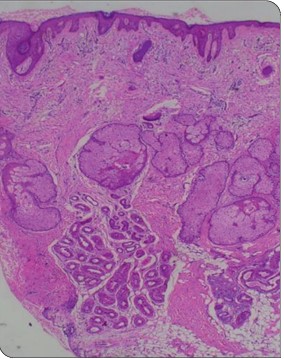

Pachydermoperiostosis, Complete Form: A Case Report of Rare Occurrence

Pachydermoperiostosis is a rare genetic disorder featuring a triad of pachydermia, periostosis and digital clubbing. It is either caused by the mutations in the HPGD (AR inheritance) or SLCO2A1 gene (AD inheritance), resulting in elevated prostaglandins E2 levels. It can be classified on the basis of presence or absence of underlying cardiac, pulmonary or hepatic disease as primary or secondary. We hereby report a case of complete form of primary pachydermoperiostosis.

PachydermiaPeriostosisHypertrophic Osteoarthropathy